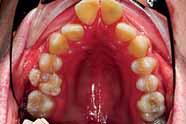

3. Anterior bite plan to reduce the overbite and bonding the lower arch (Figure 5).

The treatment of the case was planned in stages. Stage one consistedof improving the oral hygiene of the patient and management of all carious lesions and assesses the compliance and attitude of the patient towards orthodontic treatment. The next stage involved the reduction of the overbite. The patient presented with a deep overbite that was causing damage to the palatal mucosa (Figure 2). This was achieved with an anterior bite plane removable appliance and bonding of the lower arch. This appliance will free the occlusion of the buccal segment teeth and if worn consistently, will “passively” limit further eruption of the incisors but allow the lower premolars to erupt, thus reduce the increased overbite (Figure 5).